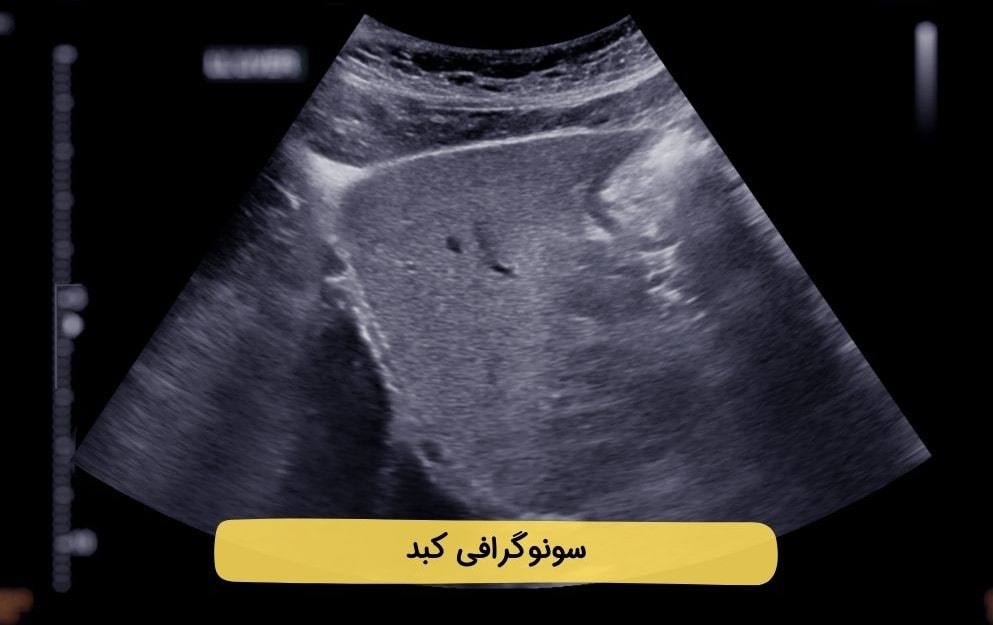

سونوگرافی کبد - تفسیر جواب و آمادگی پیش از انجام آن

خواندن برگه سونوگرافی کبد

برگه سونوگرافی شامل تصاویر و نتایج تشخیصی است که توسط پزشک تفسیر میشود. این نتایج تفسیر کاملتری شامل اندازه، شکل و وجود ناهنجاریهای کبد، کیسه صفرا یا مجاری صفراوی دارند. در صورت مشاهده هرگونه یافته غیر عادی باید براساس نتایج سونوگرافی و برنامه درمانی مناسب برای بررسی بیشتر، تصمیمگیری شود. در نهایت حتماً برای تفسیر نتایج به تخصص و تجربه پزشک معالج خود و نه تفسیرهای غیرمتخصص اعتماد کنید.